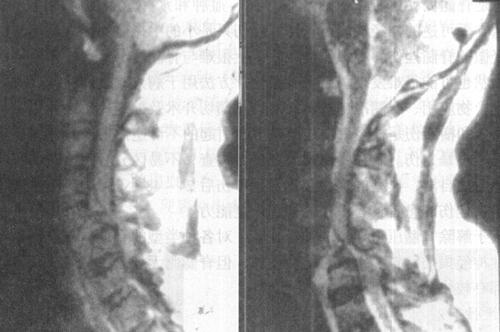

(2)出血:包括脊髓内出血和硬膜外血肿(图7-14至图7-16)、硬膜下出血和蛛网膜下腔出血等。脊髓内出血是不可逆损伤,其信号改变随时间变化较大。急性期(24h内)髓内出血灶在T1WI呈中等信号或不均匀信号,在T2WI呈中央低信号出血灶,外围水肿为高信号。亚急性期(3~5d)血肿在T1WI信号逐渐升高,在T2WI信号仍较低,慢性期血肿在T1WI和T2WI均为高信号。脊髓硬膜外血肿、硬膜下出血和蛛网膜下腔出血,在MRI上表现为椎管内脊髓外的软组织增厚影,在T1WI呈不均匀低信号,在T2WI为高信号。硬膜外出血脊髓受压移位明显。

图7-14 腰椎后柱骨折伴硬膜外出血,马尾受压。T1W(a)和T2W(b)矢状成像,椎管后方硬膜外可见T1W和T2W均为高信号的血肿

图7-15 颈髓挫裂伤:T1W(a)T2W(b)矢状面,脊髓增粒为髓水肿所致,T1W和T2W信号增高。横断面(c)脊髓内可见斑片状出血灶,硬膜外血肿T2W亦呈高信号,脊髓压迫向右后移位。颈后方软组织出血水肿,在T2W亦为高信号

图7-16 L1压缩骨折,脊髓挫裂伤:T1W(a)和T2W(b)矢状面,L1椎体呈楔状变形,椎体骨折,但无移位。后方硬膜外及脊髓内可见高信号血肿,在横断位T1W(c)、T2W(d)成像,如箭头所示脊髓圆锥内椭圆型高信号影,为出血所致。椎体骨髓水肿及出血。